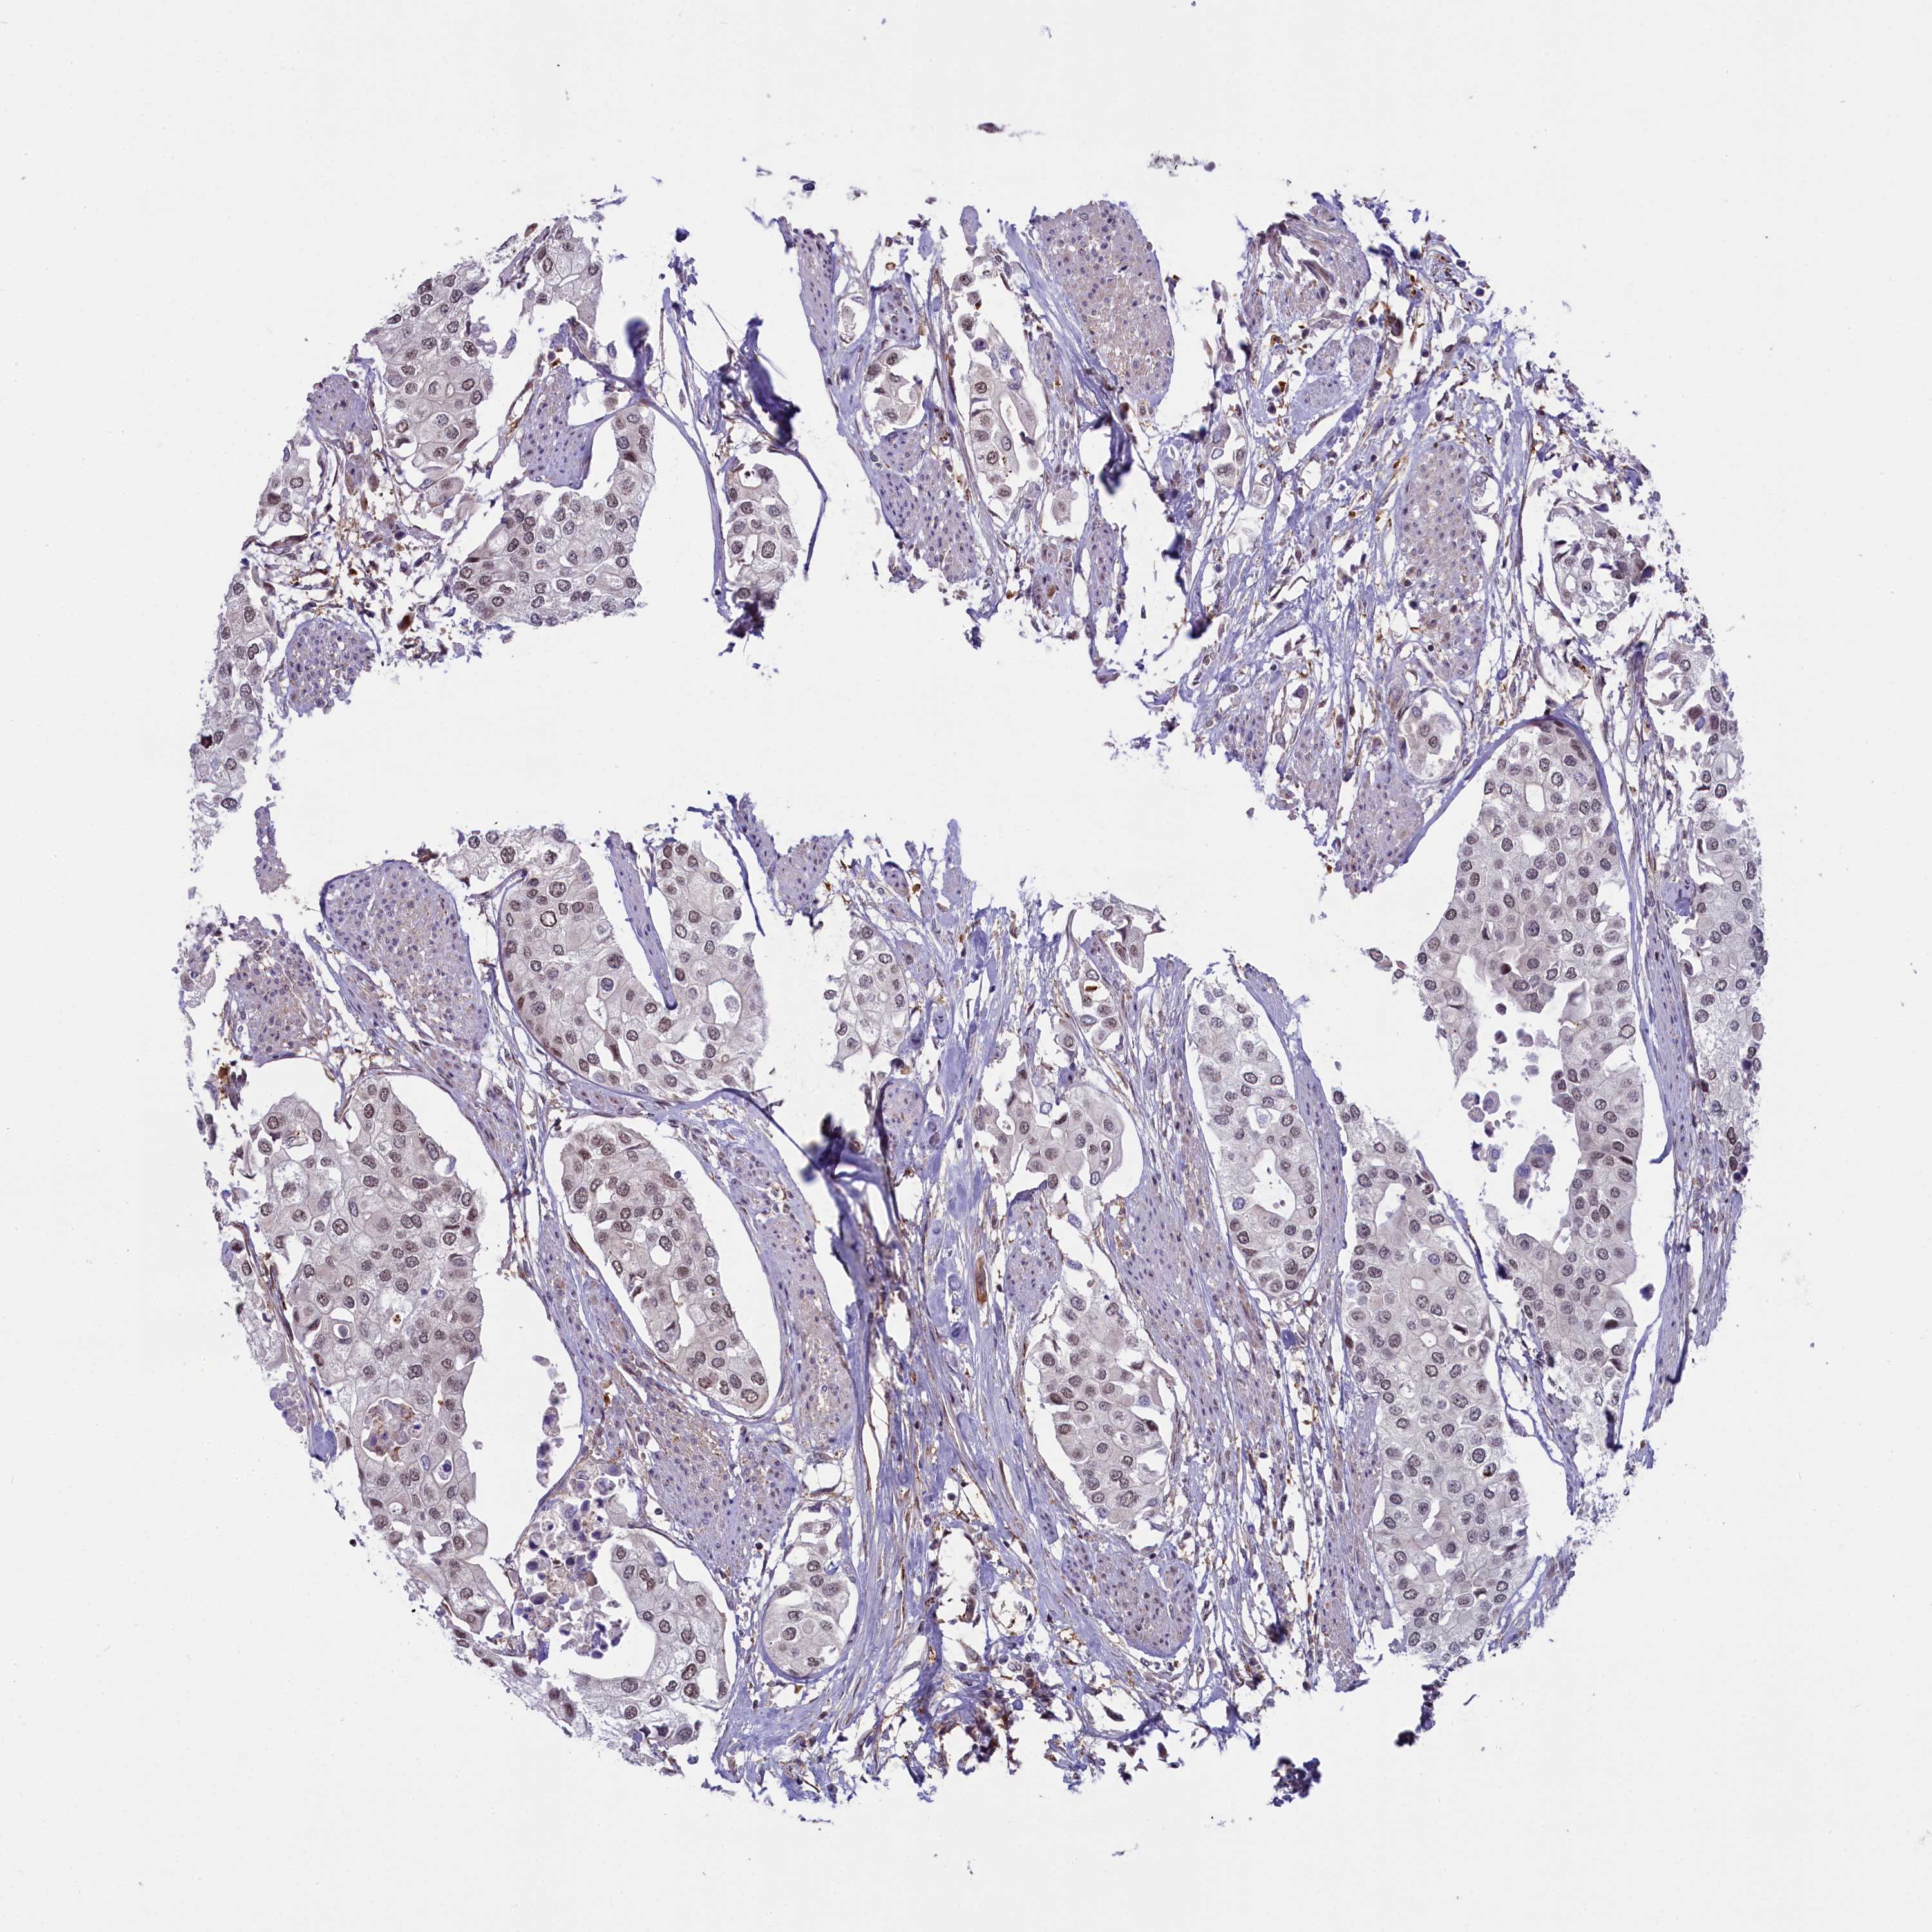

UROTHELIAL CANCER - Protein expressioni

A mouse-over function shows sample information and annotation data. Click on an image to view it in a full screen mode. Samples can be filtered based on level of antibody staining by selecting one or several of the following categories: high, medium, low and not detected. The assay and annotation is described here.

Antibody stainingi

Antibody staining in the annotated cell types in the current human tissue is reported as not detected, low, medium, or high, based on conventional immunohistochemistry profiling in selected tissues. This score is based on the combination of the staining intensity and fraction of stained cells.

Each image is clickable and will lead to virtual microscopy that enables deeper exploration of all samples and also displays staining intensity scores, fraction scores and subcellular localization as well as patient and tissue information for each sample.

Antibody HPA041653

Staining

High

Medium

Low

Not detected

Intensity

Strong

Moderate

Weak

Negative

Quantity

>75%

75%-25%

<25%

None

Location

Nuclear

Cytoplasmic/membranous

Cytoplasmic/membranous,nuclear

Urothelial carcinoma, High grade

Urothelial carcinoma, Low grade